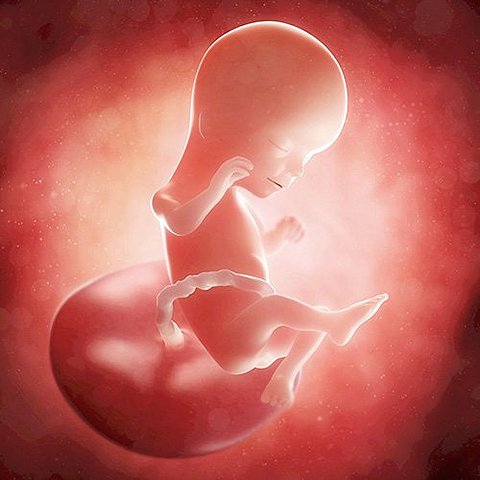

• semana 13 y 14

semana 13 y 14

A lo largo de estas dos semanas se logra considerar que el feto tienen un aspecto humano. Llas orejas están a su posición definitiva y los delgados párpados se mantendrán cerrados hasta el séptimo mes.

• semana 15 y 16

semana 15 y 16

En la semana 15 de embarazo, el bebé ya ha desarrollado lo suficiente el oído como para captar sonidos y oír la voz de la madre.

Sus antebrazos, muñecas, manos y dedos también se diferencian claramente. La futura mamá empieza a notar los beneficios del embarazo, ya que las hormonas mejoran el aspecto de la piel y del cabello.

Cerca de las 16 semanas de embarazo, en la base de la lengua se empieza a desarrollar también la glándula tiroidea, asimismo, los riñones del feto empiezan a funcionar.